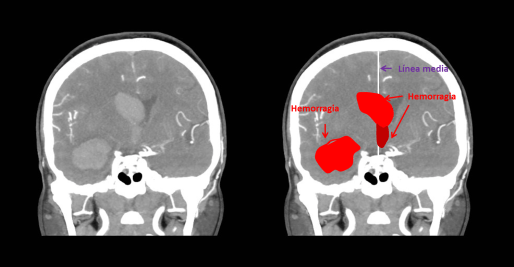

La hemorragia intraventricular primaria (HIV) consiste en la presencia de sangre únicamente en el sistema ventricular como se muestra en la figura 1. La hemorragia intraventricular se observa hasta en el 50% asociada a las hemorragias intracerebrales espontáneas (HIC) y su presencia se asocia a mayor mortalidad y morbilidad y es un factor independiente de mal pronóstico. En adultos la HIV primaria es una causa infrecuente de hemorragia intracerebral.

En algunos casos, como el caso de la Figura 1, no es posible demostrar la causa a pesar de realizar una angiografía convencional.